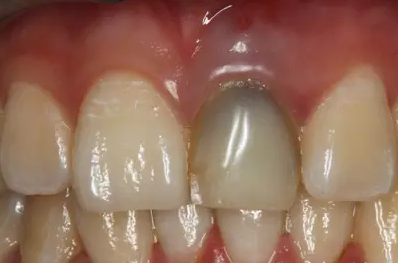

患者外院螺紋樁核加樹脂冠

唇側(cè)出現(xiàn)瘺管